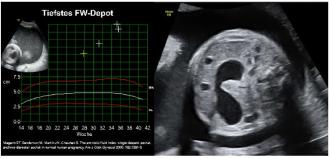

Beispiel 2: Hier liegt das klassische Bild einer Duodenalstenose vor mit „double bubble“ und progressivem Polyhydramnion.